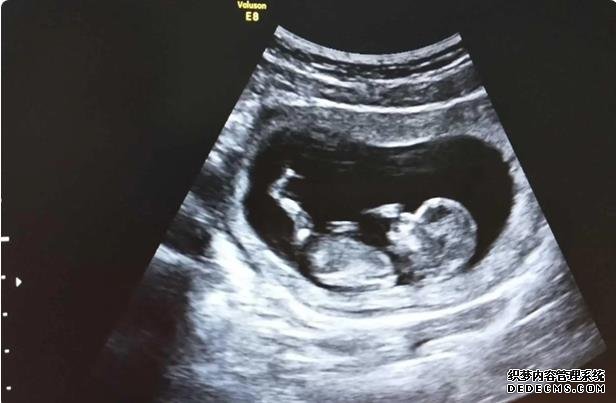

在胡主任那里看診了之后,現在有一個比天使還可愛的孩子!她就是我生命的全部!謝謝胡媽媽送子。